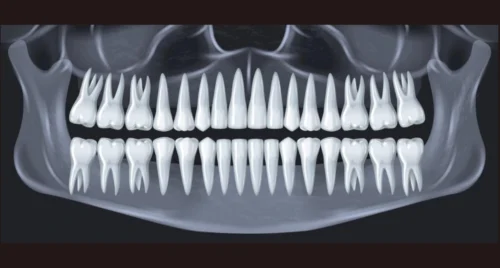

Estudios 2D

- Radiografía periapical individual.

- Radiografía periapical individual milimetrada.

- Radiografía periapical completo con tecnica de cono paralelo.

- Radiografías coronales.

- Radiografía Oclusal.

- Radiografía Panorámica.

- Radiografía Cefálica Lateral.